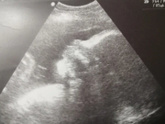

5 марта 2022 23:48 Вот и прошло 4 года как нас с тобою разлучили? Я не надень не забывала о тебе и никогда не забуду. Ты был со мной долгие и счастливые 27 недель,но на верху решили иначе,все так же помню и люблю.